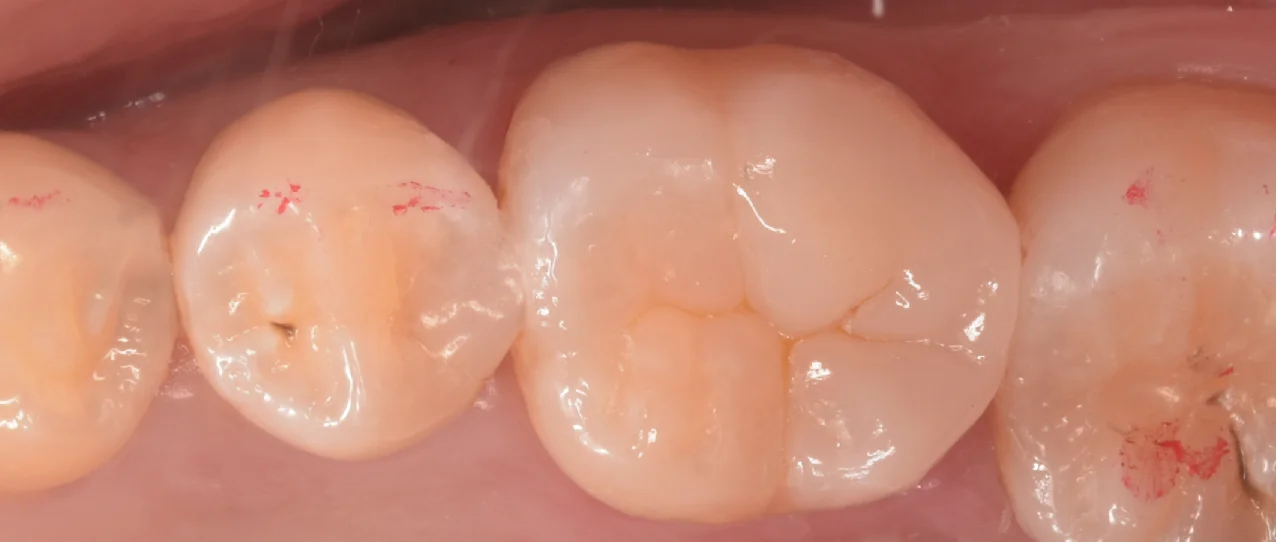

詰め終わった写真がこちらになります。

噛み合わせの部分がすでにCAD/CAMインレーに置き換わっていたため、流石に噛み合わせの調整は結構することになりましたね・・・。

歯とのギャップもなく適切な形態も付与できているので今までより歯が少なくなってはいますが、今までよりも長期予後は期待できるはずですよ。